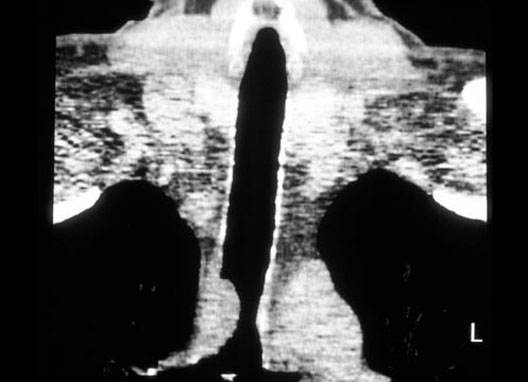

Trachea Cancer

1. Trachea cancer

2. Trachea